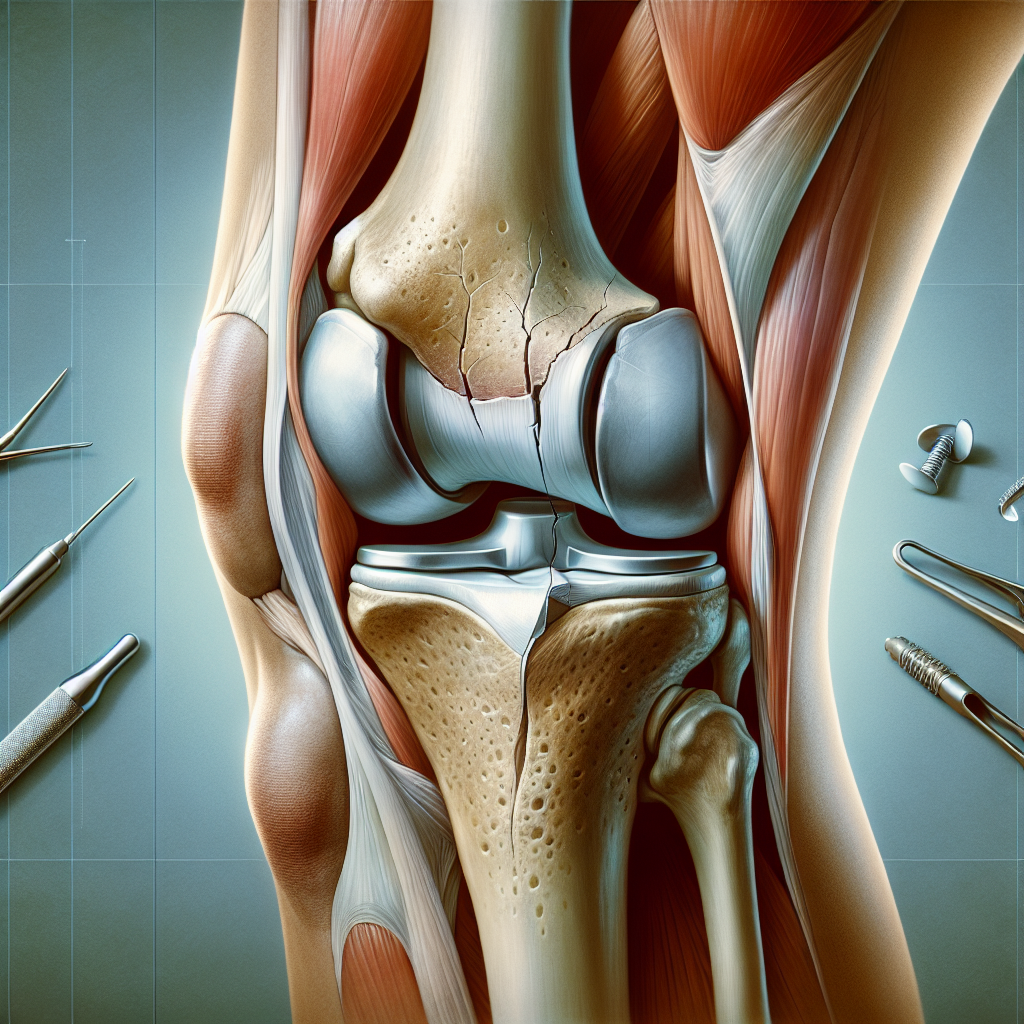

A fracture of the medial femoral condyle is an injury that often requires immediate orthopedic attention, as the proper alignment of the femur and knee cartilage is crucial for maintaining knee function and preventing future complications such as arthritis. Due to the nature of this fracture, which involves the femoral condyle—the rounded end of the femur that articulates with the tibial plateau—ensuring precise alignment is essential.

The medial femoral condyle is located on the inner side of the knee, close to the midline of the body. Fractures here can occur due to a shearing force that typically affects the cartilage surface. This type of fracture is more commonly witnessed in children, as their bones are generally weaker than their tendons and ligaments. In adults, the reverse is true; a traumatic event that might fracture a child’s condyle will likely cause softer tissue damage, such as a ligament injury, in adults.

For a medial femoral condyle fracture, surgical intervention is not always necessary but may become crucial if there is any displacement. The key concern with this fracture is ensuring that the articular cartilage—the smooth, white tissue that covers the ends of bones where they come together to form joints—is not disrupted. If the fracture site isn’t aligned perfectly, it may result in a step-off in the cartilage, which could accelerate wear and tear, ultimately leading to osteoarthritis.

- Surgical Procedure: Typically involves using a combination of plates and screws to ensure accurate alignment of the fragments. This hardware stabilizes the fracture, maintaining the correct position while new bone forms and heals.